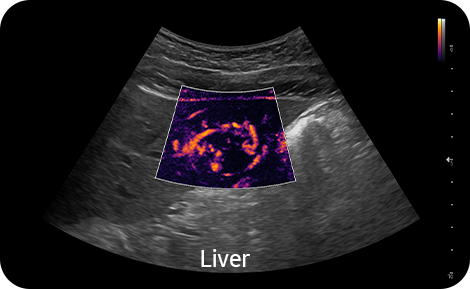

Contrast Enhanced Ultrasound

CEUS+ ¹ is a contrast agent imaging technology. The micro-bubble contrast agent injected into the body through the vein or alike is subjected to perform nonlinear resonance due to stimulation of ultrasound energy.

Visualize slow flow

in microvascular vessels

MV-Flow™ ¹ visualizes microcirculatory and slow blood flow to display the intensity of blood flow in color.